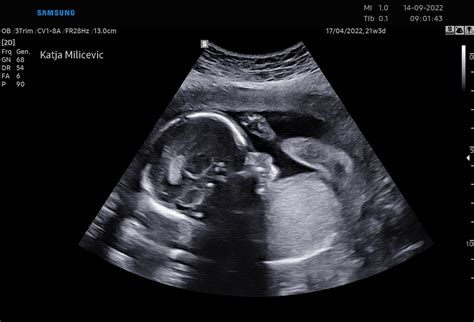

V 23. tednu nosečnosti vaš otrok hitro pridobiva na teži. Njegova koža je še vedno prosojna in se zdi, kot da mu je malce prevelika, saj raste hitreje kot njegovo telo, ki jo nato s kopičenjem maščob in rastjo dohiti. Zdaj bi že morali občutiti redno gibanje svojega otroka. Otrokove okončine so zdaj v pravem sorazmerju, vaše malo bitjece pa postaja vedno bolj podobno ljubkemu dojenčku, ki ga pričakujete. V naslednjih nekaj tednih boste čutili premike teh daljših okončin, saj je otrok še naprej zelo aktiven. Telesna teža otroka v tem tednu je okoli 450 gramov, kar je približna vrednost.